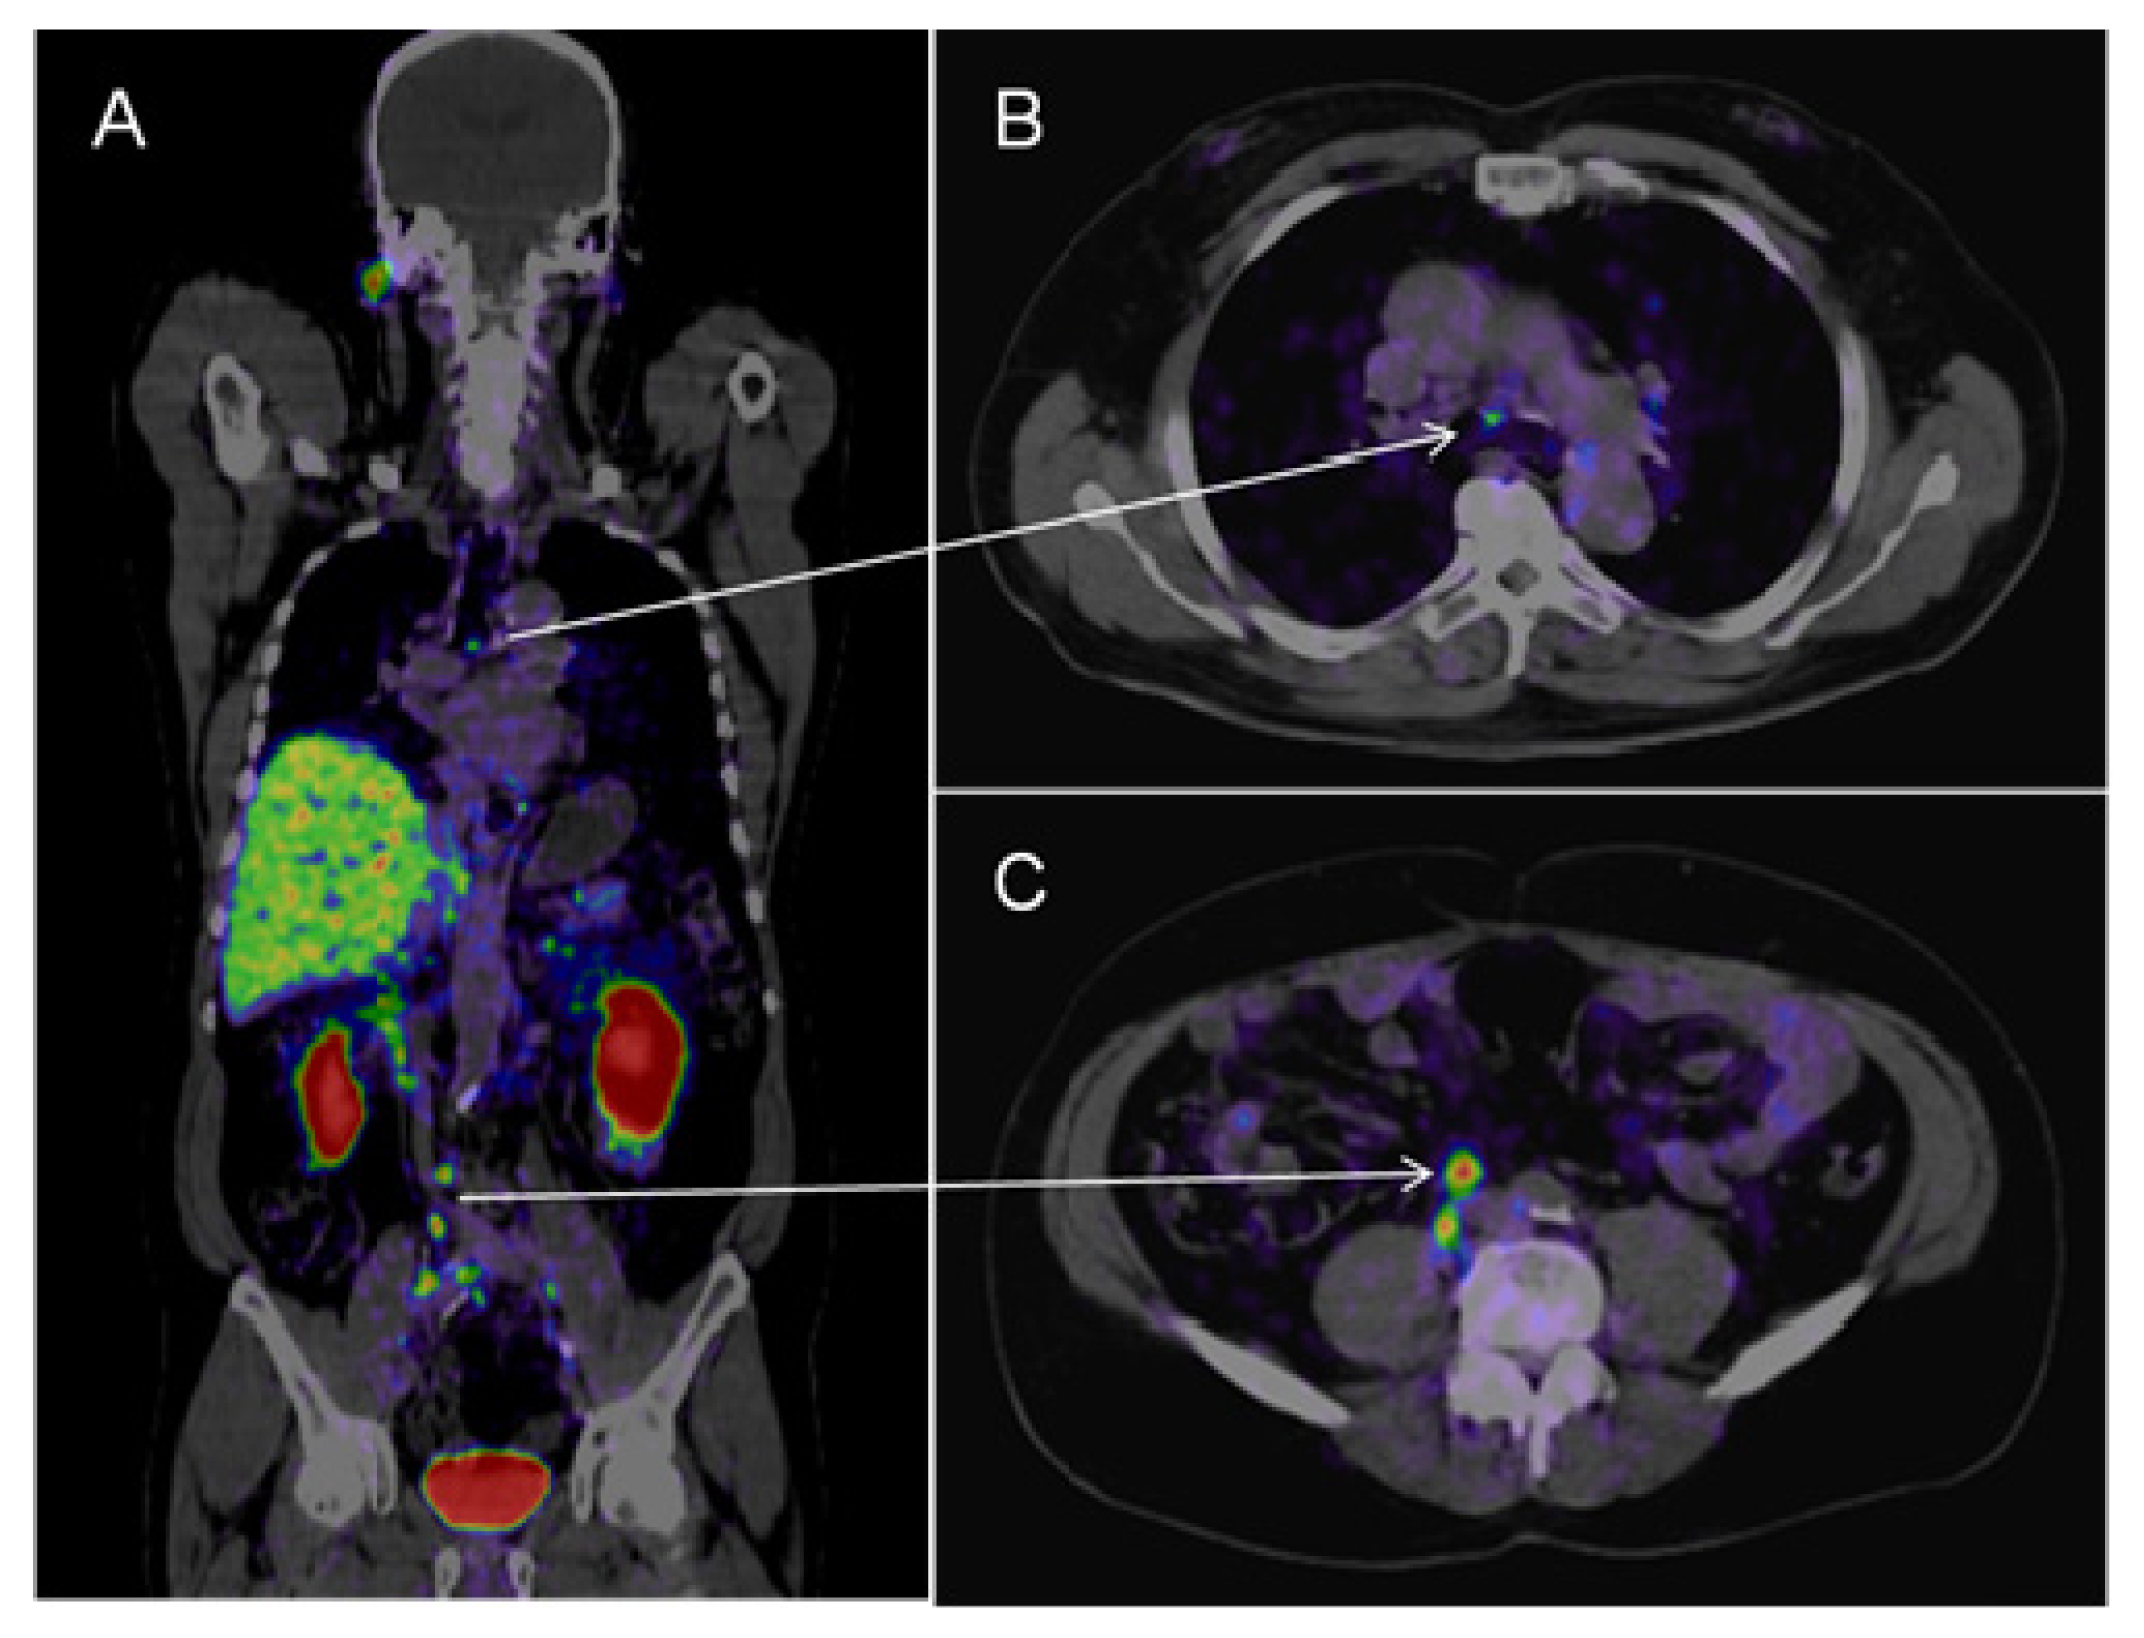

Afshar-Oromich et al. showed promising results in an initial study in 37 patients. They observed excellent contrast uptake, also in small lymph nodes (see Figure 2) [43]. In direct comparison to 18F labeled Choline, first results suggest that PSMA-targeted imaging performs better in detection of small lymph nodes in patients with low PSA values [44]. If these results are reproducible this may have significant clinical impact on diagnosing prostatic lymph node metastases.

Figure 2.

68Ga-PSMA-PET-CT. Patient with prostate cancer (status after brachy-therapy and bilateral iliac lymph node dissection, current PSA 21 μg/L). PET images were acquired after the administration of 68GA-PSMA-Ligand (60 min thereafter). The figure shows fused images (PET-CT): On the coronal view (A) a pathologic isotope uptake in multiple lymph nodes in the right para-iliac region and infra-carinal (mediastinum) is clearly visible; the corresponding transversal images show the para-iliac (B) and infra-carinal (C) lymph nodes with elevated uptake of the tracer. The corresponding transversal native CT images present these suspect structures (D,E) as normal sized lymph nodes (marked by red arrows).